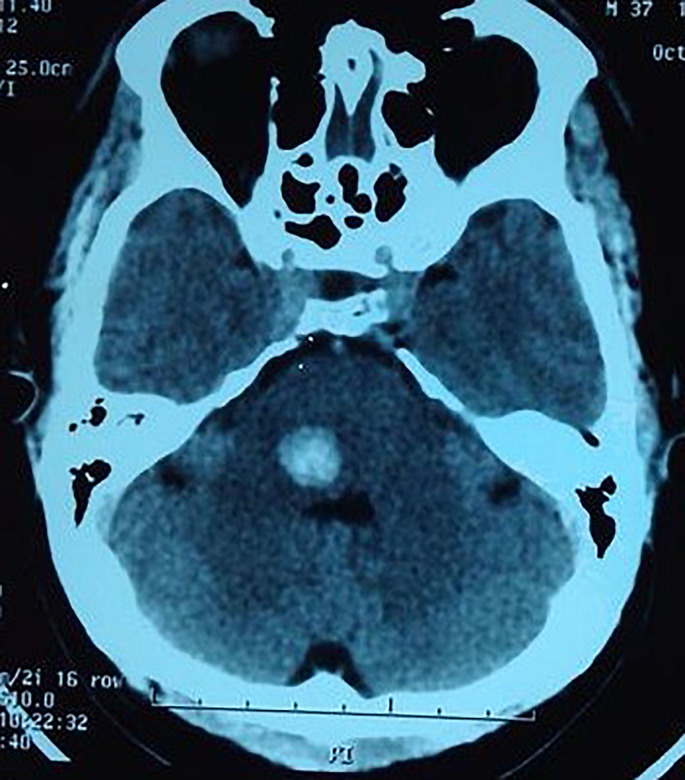

Background: Many unusual and fascinating causes of stroke are seen in Asia. Although rarely encountered in the Western world, such cases are seen not so infrequently by neurologists, physicians, and other healthcare workers in Asian countries. This article highlights some of these intriguing causes of stroke such as snakebite, scorpion stings, and bee and wasp stings.

Summary: Snakebite is a neglected tropical disease of global importance affecting over 5 million people each year, and scorpion stings and bee and wasp stings affect over a million people worldwide every year. Strokes due to these uncommon causes predominantly affect young males in their most productive years, and many victims die or remain with residual disability with significant socioeconomic consequences to the affected families and society. Both ischaemic and haemorrhagic strokes are seen, with ischaemic strokes being more common. Many unanswered questions remain regarding the pathophysiological mechanisms, clinical spectrum, and the natural history of stroke due to these causes. Antivenom is effective in snake envenoming, antivenom and prazosin are effective in scorpion envenoming, and treatment of anaphylaxis and allergy is recommended in systemic reactions due to bee or wasp stings. However, there are no treatment guidelines or expert recommendations to guide the management of stroke in these patients, and there are no data on the safety and efficacy of stroke-specific treatments such as antiplatelet therapy, thrombolysis or endovascular treatment.

Key messages: More research is clearly needed to unravel the complexities related to stroke following snakebite, scorpion envenoming, and bee and wasp stings, and to guide the development of optimal stroke treatment strategies in these unusual situations. Awareness of these exotic stroke aetiologies is important in early recognition and appropriate management of patients presenting with stroke symptoms in Asian countries, and in global travellers from the region. International collaborations would go a long way in improving our understanding of these rare but fascinating causes of stroke.